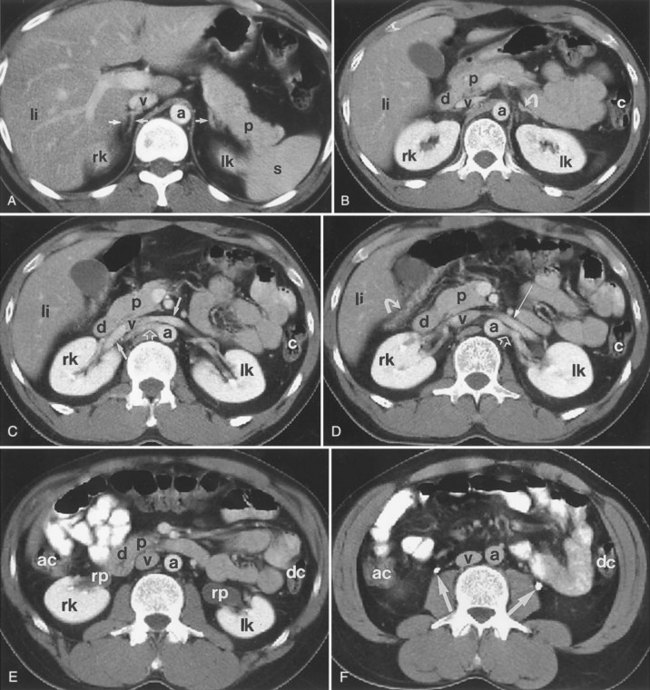

It is helpful during scanning of the kidney to understand its anatomic position within the retroperitoneum. This assists identifying the midsagittal plane, which serves as a reference point for a complete examination (Fig. 4–31).

Figure 4–31 The lower pole of the kidney is displaced 15 degrees laterally compared with the upper pole (A). The kidney is rotated 30 degrees posterior to the true coronal plane (B). The lower pole of the kidney is slightly anterior compared with the upper pole.